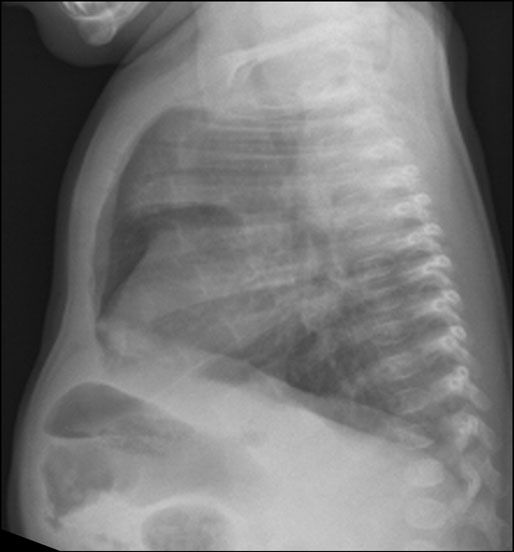

Figure 2 – Initial chest radiographs showed right upper lobe consolidation.

Laboratory tests and radiographic evaluation. Initial laboratory results indicated a slightly low ionized calcium level and an elevated alkaline phosphatase level. Chest radiographs showed right upper lobe consolidation (Figure 2). Pulmonology, ophthalmology, genetics, endocrinology, and gastroenterology specialists were consulted.